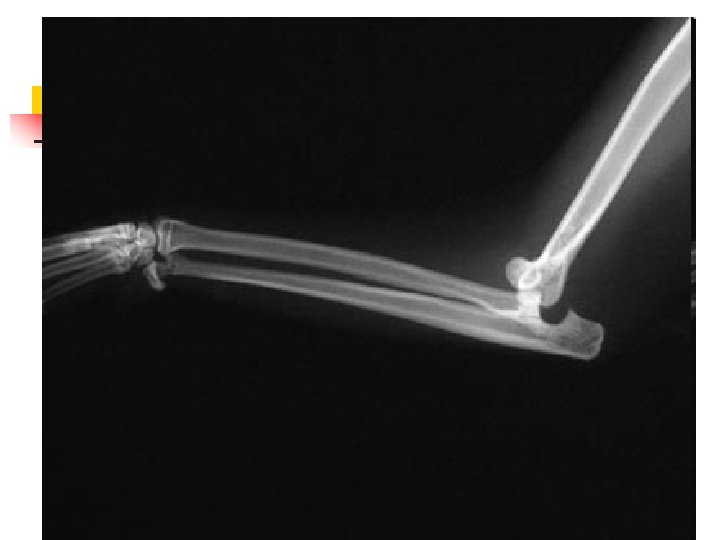

When Animals Limp n n n The good new is that 9 out of 10 limping animals have what we call soft tissue injuries a sprain, a pull, a bruise and only require exercise restriction to heal. However, 1 out of 10 animals with lameness has something more serious, and we can tell which ones by close observation of the patient walking and careful physical examination. In those cases, radiographs are used to make a diagnosis.

When Lameness isn’t Simple n n Sometimes when an animal limps the cause turns out to be something more serious than a simple injury. The doctors palpated a firm, painful lump in the leg this dog was favoring. Radiographs showed that the bone was expanded in that area, with a motheaten, hollowed-out center. These are classic signs of a tumor in the bone, known as an osteosarcoma.